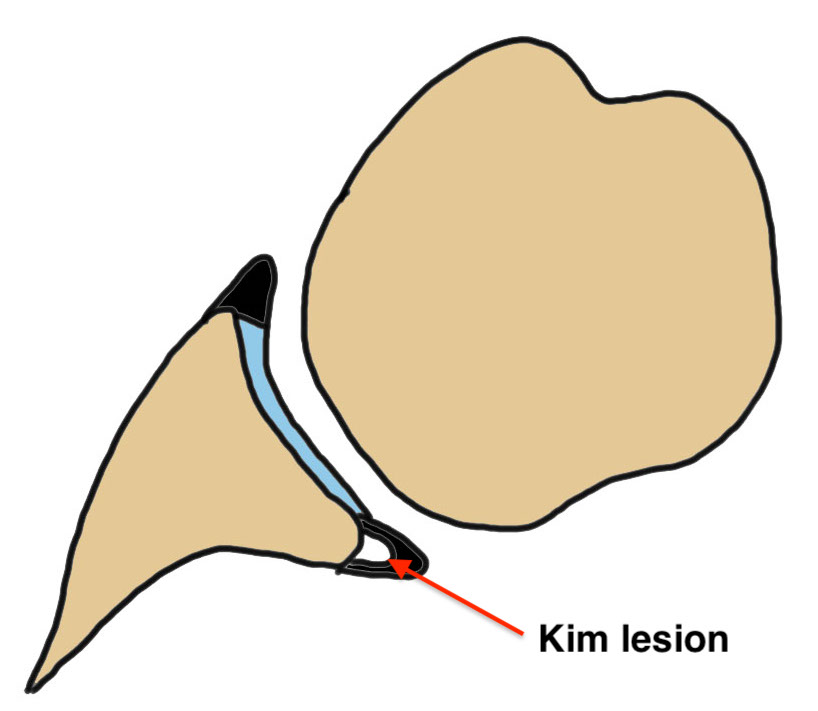

Kim lesion

- Kim lesion

- incomplete and concealed avulsion of the posteroinferior labrum

- superficial portion attached, deep portion detached

- labrum flat with loss of normal height resulting in retroversion of the chondrolabral glenoid